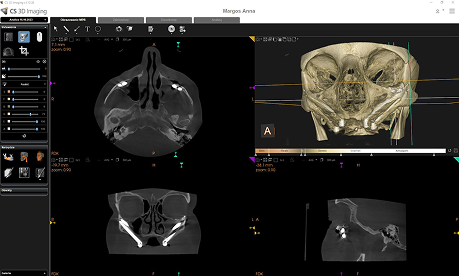

APARAT CS 9600 3D

Posiadamy jeden z najdoskonalszych aparatów z rodziny Carestream – CS 9600 3D, który zapewnia wyjątkową precyzję i komfort w diagnostyce medycznej i stomatologicznej. W jego konstrukcji znajdziemy innowacyjny tomograf CBCT, pantomograf oraz przystawkę do zdjęć cefalometrycznych, co zapewnia kompleksową opiekę diagnostyczną w jednym urządzeniu.

Trójwymiarowy obraz w diagnostyce uzyskujemy dzięki możliwościom nowoczesnego aparatu CS 9600 3D, który umożliwia obrazowanie przestrzenne, dzięki użyciu Stożkowej Tomografii Komputerowej CBCT. Za pomocą tomografu komputerowego oceniamy w trójwymiarowej przestrzeni